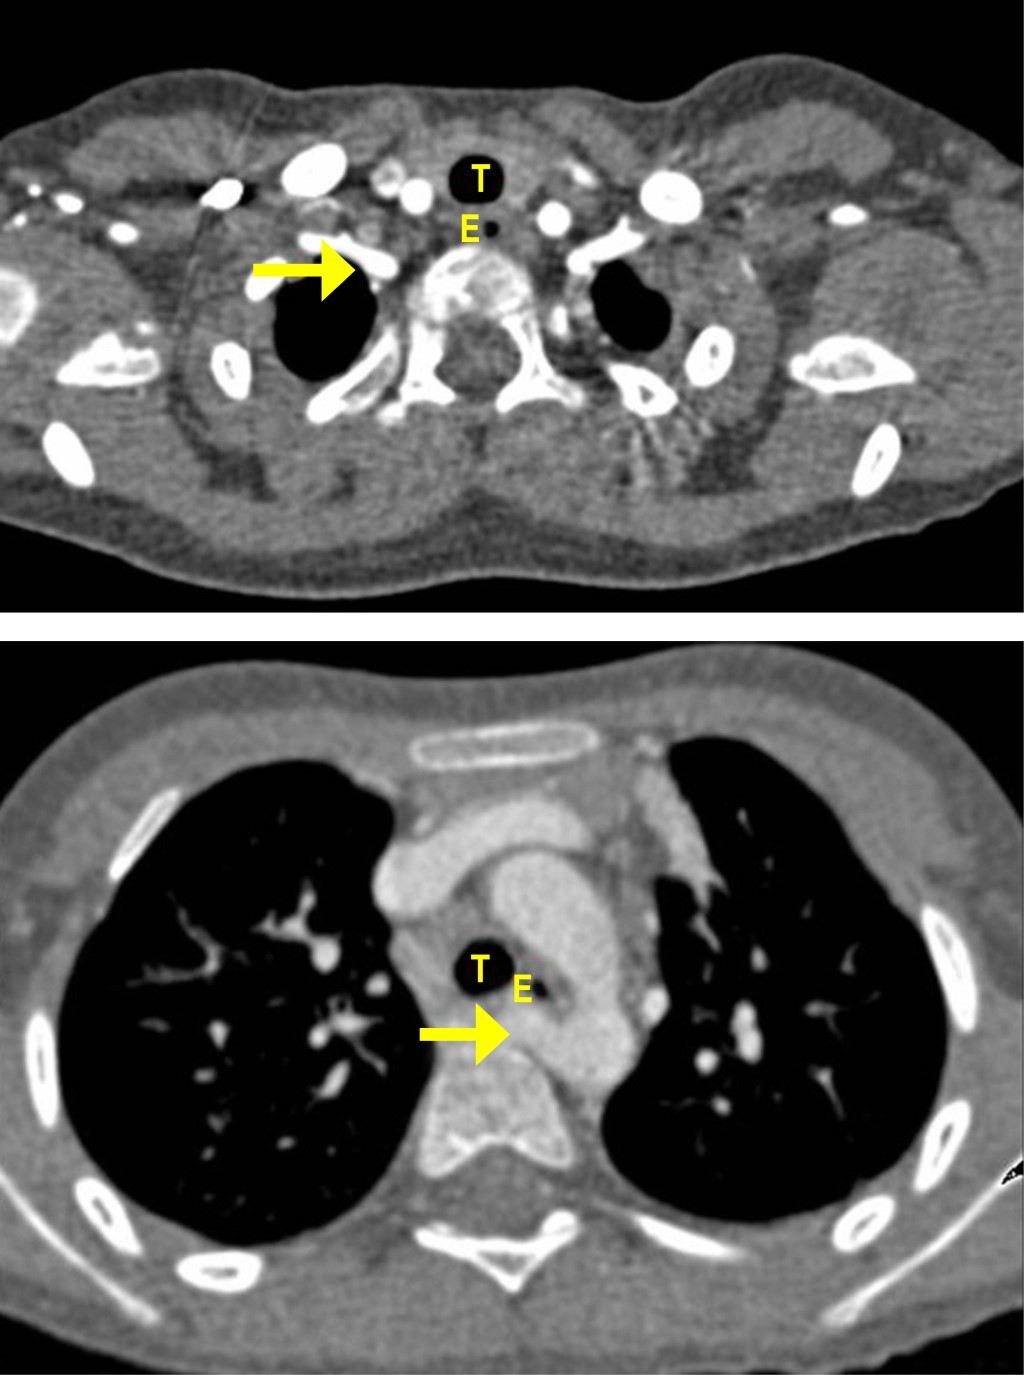

Estudios: difusión de monóxido de carbono (DLCO) 7.5 mL/min/mmHg (valor predicho 10.2), espirometría posbroncodilatador con una respuesta en volumen espiratorio forzado en el primer segundo (FEV1) del 16% y de más de 200 mL. La radiografía de tórax muestra un patrón atelectásico (Figura 1). Serie esofagogastroduodenal (SEGD) con presencia de reflujo grado III; en la angiotomografía de tórax (angio-TC) se observa una subclavia derecha aberrante (Figura 2), lo mismo que en la aorta descendente, también un vaso aberrante (Figuras 3 y 4).

Por otra parte, las técnicas de imagen son pruebas complementarias que confirmarán el diagnóstico. La radiografía de tórax puede proporcionar información sobre el desplazamiento del arco aórtico o la tráquea, la presencia de una estenosis traqueal, así como infiltraciones pulmonares, distelectasias o atelectasias como signos de compresión de las vías respiratorias.9 El esofagograma muestra la indentación esofágica; sin embargo, la información anatómica obtenida no es lo suficientemente precisa para el tratamiento terapéutico, por lo que se requieren imágenes transversales como la tomografía computarizada (TC) o la resonancia magnética (RM). Se pueden usar métodos de posprocesamiento para generar datos 3D, tanto de la TC como de la RM, dando una vista detallada de la morfología vascular.10 En cuanto a los estudios de radiología la SEGD no reveló identaciones esofágicas, sólo la presencia del reflujo severo; tampoco la tele de tórax mostró imágenes radiológicas sugerentes de las malformaciones, por lo que no fueron concluyentes para el diagnóstico. Por lo tanto, la TC de tórax y la angiotomografía son los estudios de elección para el diagnóstico de los anillos vasculares y de las malformaciones pulmonares como lo es el secuestro pulmonar intralobar o extralobar, la otra patología agregada en nuestro paciente.